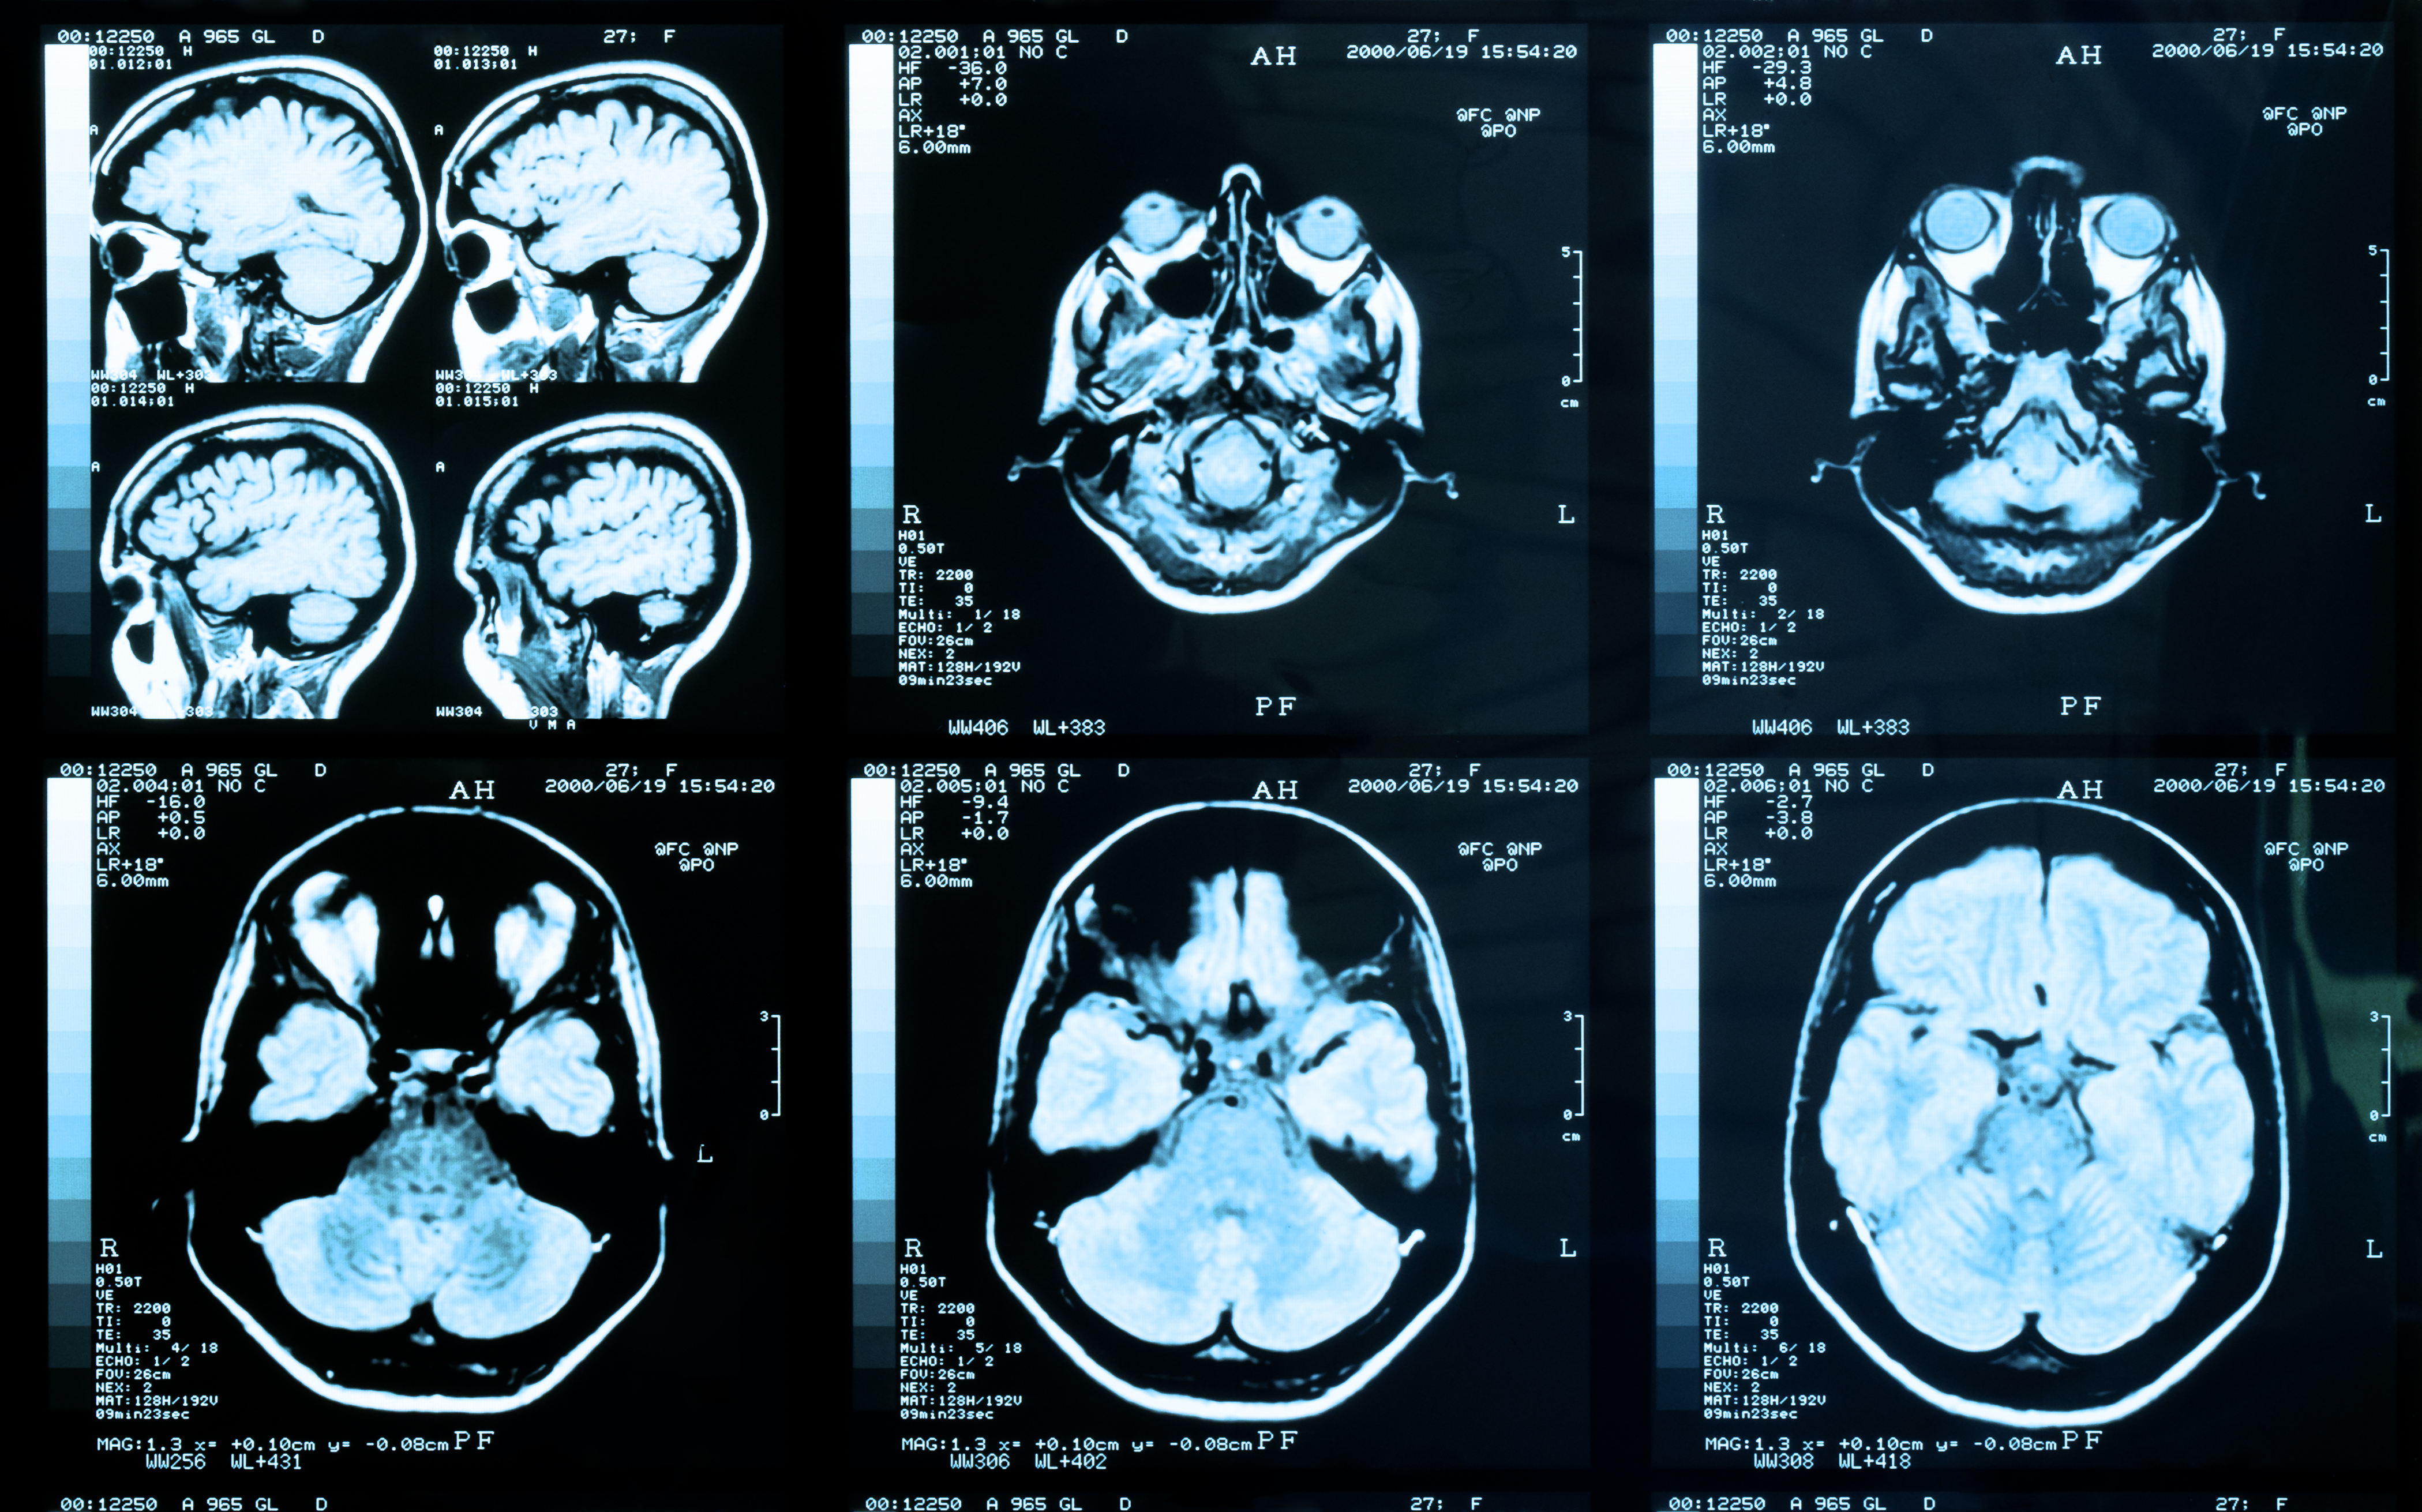

B-SNIP’s starting point was to take approaching 1000 patients with 1 of 3 conventional diagnoses – schizophrenia, schizoaffective disorder and psychotic bipolar disorder – and measure a wide range of cognitive variables, electrophysiological variables such as auditory evoked potentials, and aspects of eye movement, along with structural and functional MRI.

The 201 patients studied had a baseline, pre-treatment MRI. This was assessed in relation to outcome at four weeks, using PANSS criteria, at which point 68% of patients in this subset were considered to be in remission. Various structural brain measures were used, notably mean cortical thickness in 31 regions, surface area and a local gyrification index of cortical folding. There were also measures relating to subcortical regions. The bottom line is that none of these baseline MRI measures predicted clinical outcome.

Perhaps, Dr Lawrence speculated, four weeks is too short to assess any correlation. Perhaps the study was compromised by heterogeneity in imaging and assessment between the many sites involved. Or perhaps brain structure is simply not that a good predictor, and other imaging modalities – or different biomarkers entirely, such as those relating to inflammation -- would give us a better handle on processes underlying the disease and its response.

A second context in which prediction would be highly useful is in distinguishing people at high risk of having a first episode of psychosis. And it seems that increased connectivity in a cerebellar-thalamo-cortical network is indeed predictive of conversion to psychosis in people at clinically high risk, according to data from the NAPLS study presented by Tyrone Cannon (University of Yale, New Haven, Connecticut, USA).

Abnormality of brain architecture – which can be seen in both task-related and resting states -- is more pronounced among converters than non-converters and predicts time to conversion

Investigators from the North American Prodrome Longitudinal Study consortium have demonstrated that this abnormality of brain architecture – which can be seen in both task-related and resting states -- is more pronounced among converters than non-converters and predicts time to conversion. By way of validation, they have also confirmed that this pattern of hyperconnectivity is present in patients with established schizophrenia.4